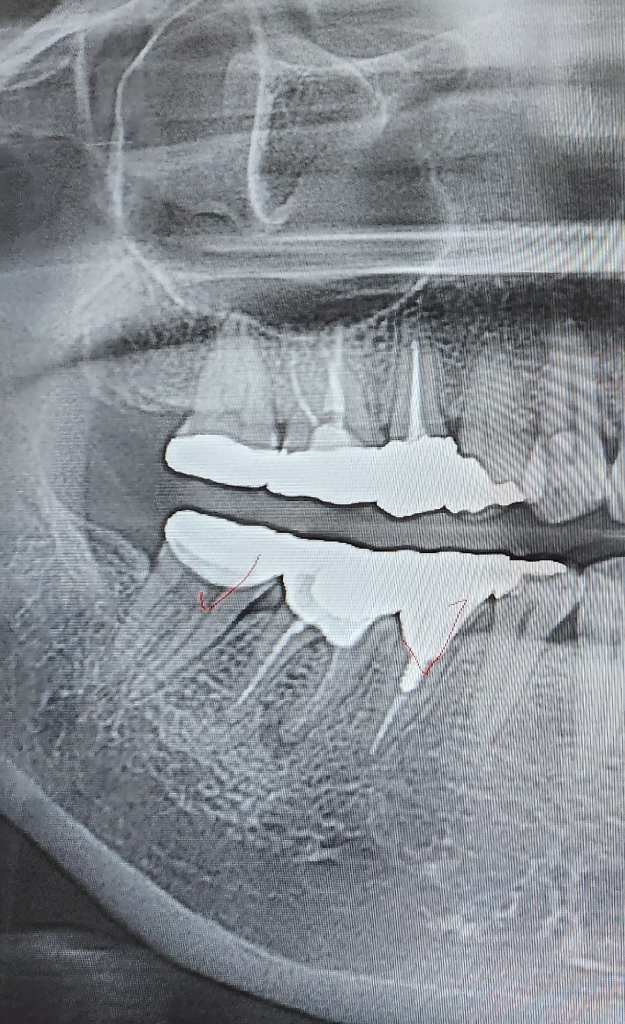

사진으로만 봤을 경우에는 #46 치아 뿌리끝에 약간의 염증이 보이고 있습니다.

잇몸이 내려간것은 크게 문제가 되지는 않을것으로 보이나 뿌리끝의 염증으로 인해서 생기는 통증이라면 재신경치료가 필요할수 있습니다.

일반병원에서는 재신경치료를 잘 하지 않습니다. 성공률이 높지 않기 때문입니다. 뿌리끝에 약간의 염증이 보이고 잇몸이 부워잇는 상태이신거 같은데 잇몸치료를 조금더 받아보시고 크라운치료를 마무리 하시는게 어떠실지요.